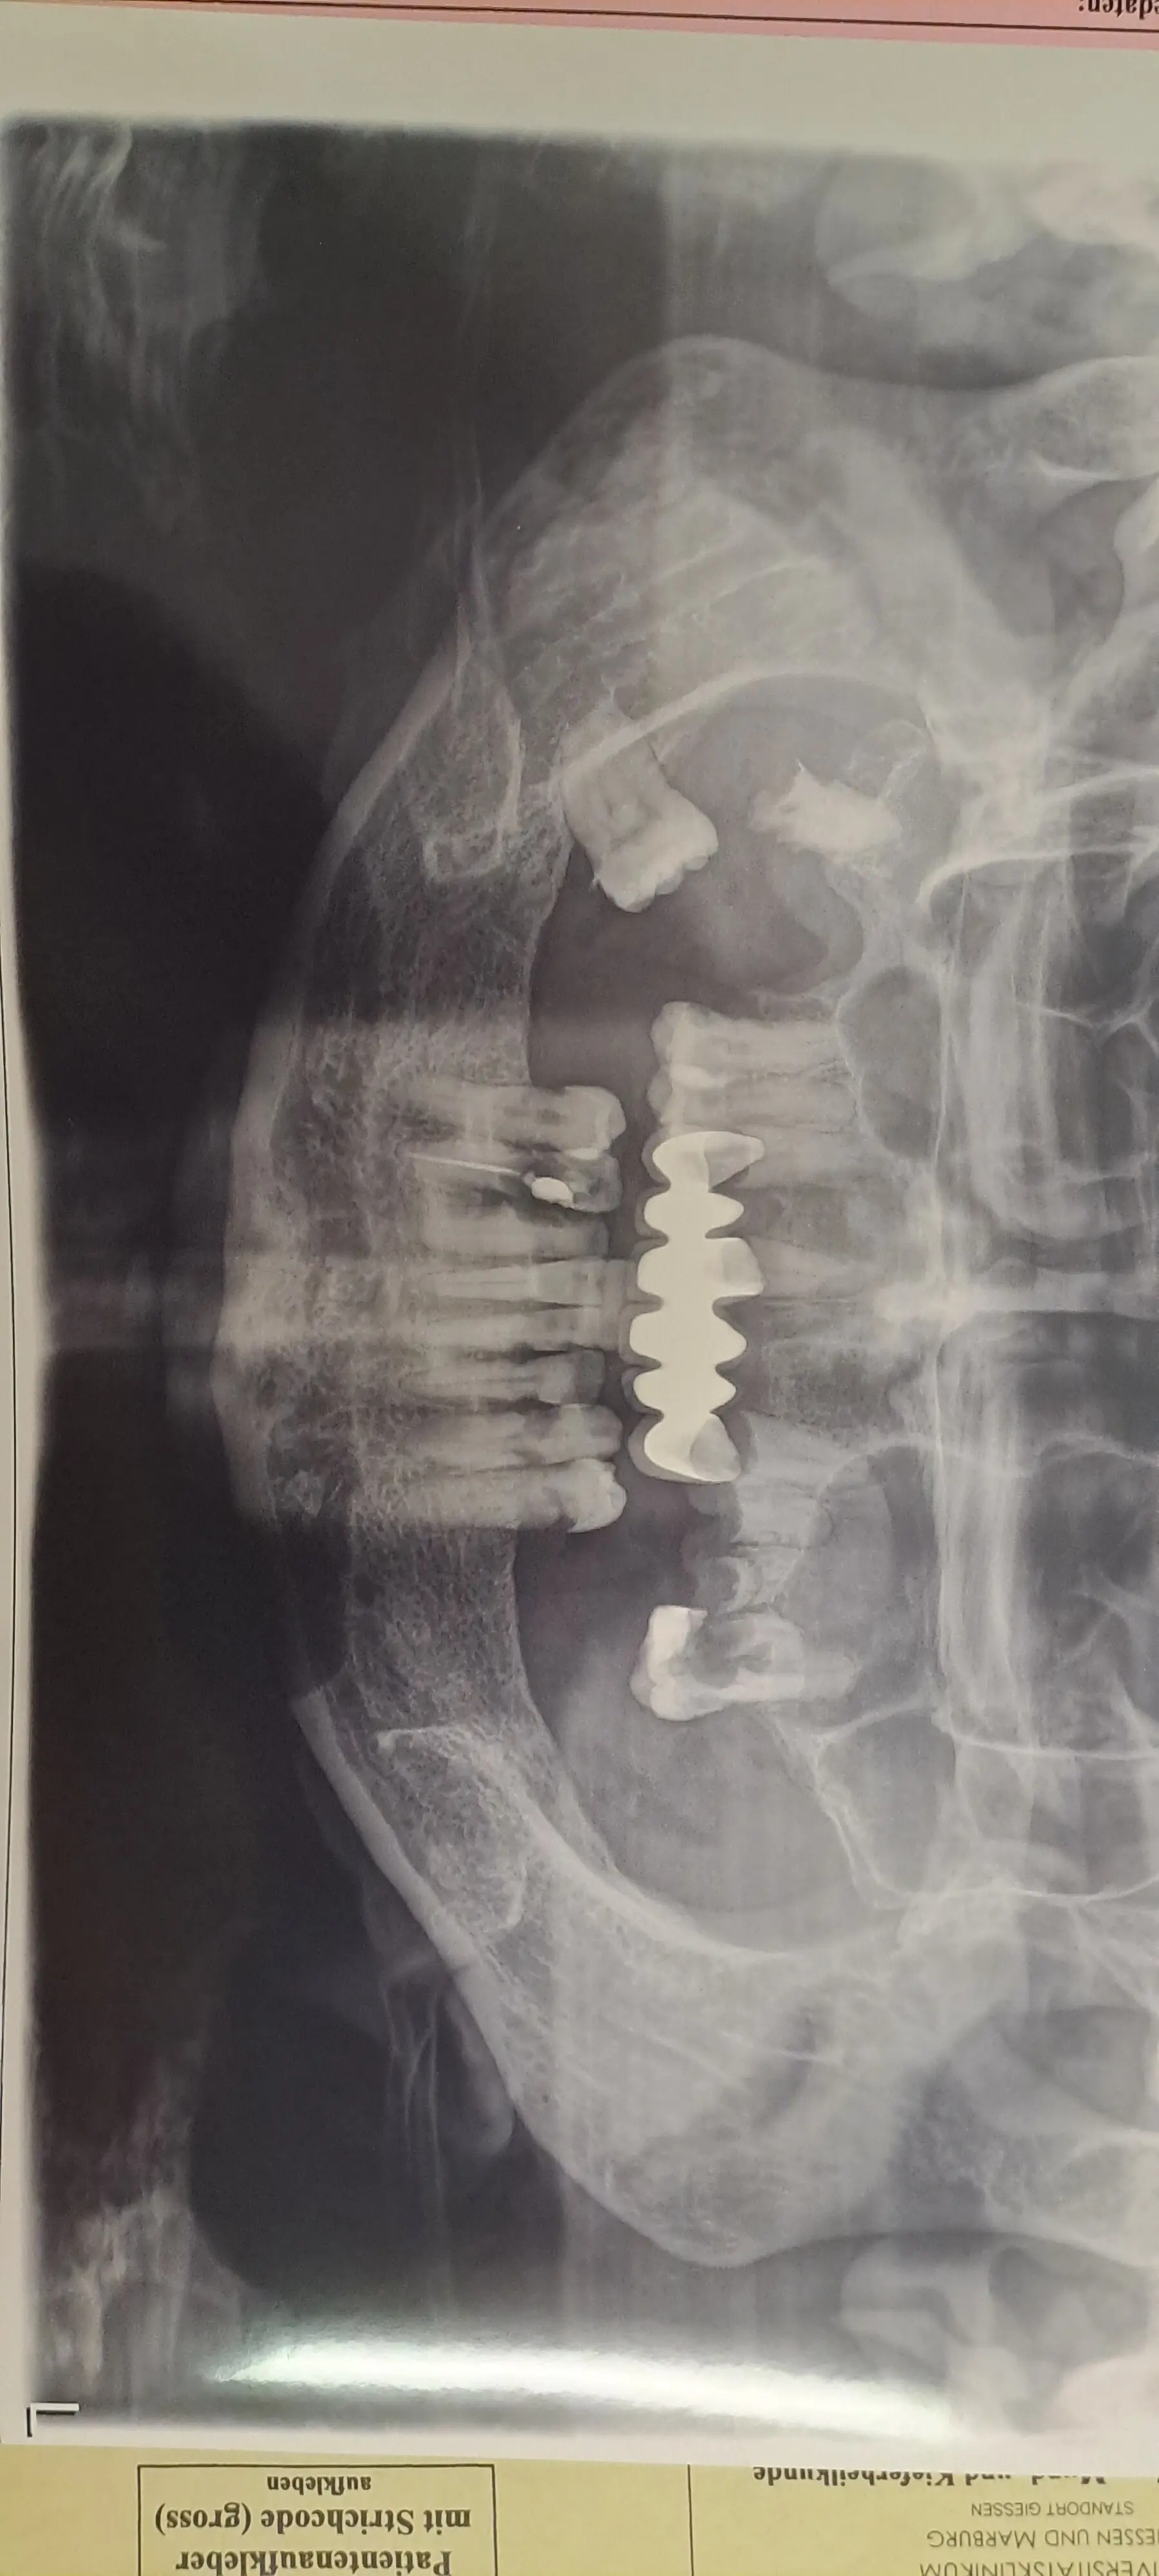

Здравейте! Заминахме зо Германия,там бях прегледана от инфекционист,като в последствие ме препрати към Лицевочелюстна хирургия,защото така  и неизясненото ми състояние е разрушило венците и всичките ми зъби,поради сринатият имунитет и налични инфекций! В Германия искат да извадят всичките ми зъби,да направят пластика,трябва да се изчистят и синусите ,защото инфекцията е близо да мозъка ми!

Hello! We went to Germany,where I was examined by an infectious disease specialist,and subsequently referred to maxillofacial surgery,because my never explained condition has destroyed my gums and all my teeth,due to the collapsed immunity and existing infections! In Germany they want to take out all my teeth,do a plastic surgery,need to clean my sinuses too ,because the infection is close to my brain!